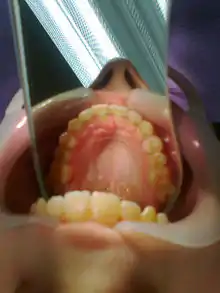

После завершения исправления прикуса, ретейнер фиксируется специальным композитным материалом на лингвальную (внутреннюю) поверхность передних шести зубов и носится там до полного завершения ретенционного периода и стабилизации зубов в новом положении. Вреда зубам ретейнер не приносит. Его устанавливает ортодонт, сразу после снятия брекет-системы. Привыкание к ретейнеру примерно 1 неделя и пациент перестаёт его замечать. Во время ретенционного периода необходимо пользоваться ирригатором со специальной насадкой для более тщательного ухода за зубами и ретейнером. Срок ретенционного периода зависит от сложности исправления прикуса и времени исправления прикуса брекет-системой.